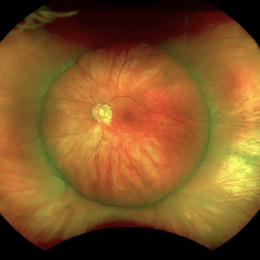

Stage 3 Coats' Disease

Stage 3 Coats' Disease

Aug 7 2022 by Muhammad Amer Awan, MD, FRCSEd, FRCOphth, FRCS Glasgow, FACS, FASRS

Fundus photography of a 6 months old baby boy who presented with unilateral leucoria. There was right exudate retinal detachment with extensive hard exudates and tortuous retinal vessels. Diagnosis of Coats' disease was made that was externally drained and intravitreal rhanibizumab was given.

Photographer: Muhammad Amer Awan, Shifa Taamer e Millat University

Condition/keywords: Coats' disease, exudative retinal detachment, exudative retinopathy, unilateral exudative retinal detachment